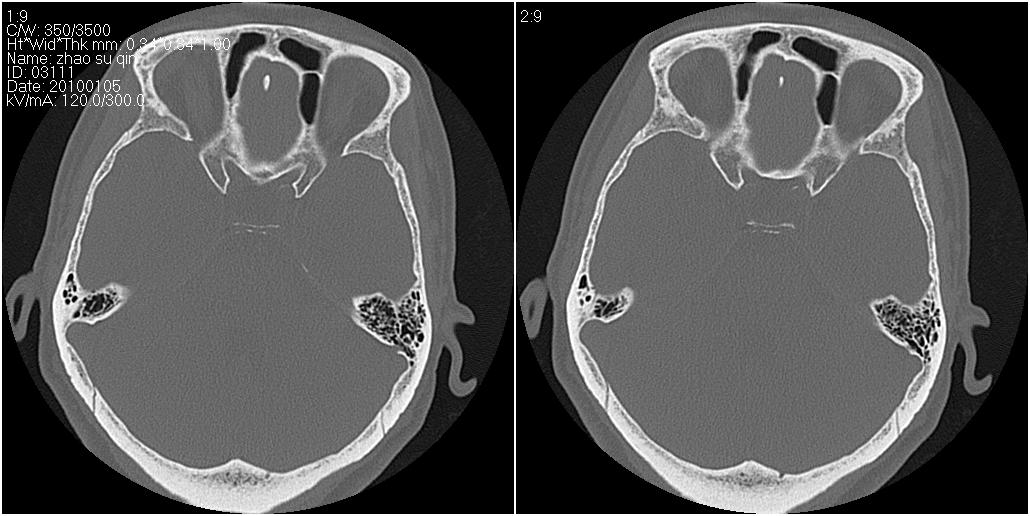

标题: CT24015:一个头部外伤患者进行鉴定,除了左侧筛板骨折,哪 [打印本页]

标题: CT24015:一个头部外伤患者进行鉴定,除了左侧筛板骨折,哪

1)左侧筛板骨折。2)双侧筛窦炎症(或积血)。

其余未见明显骨折征。